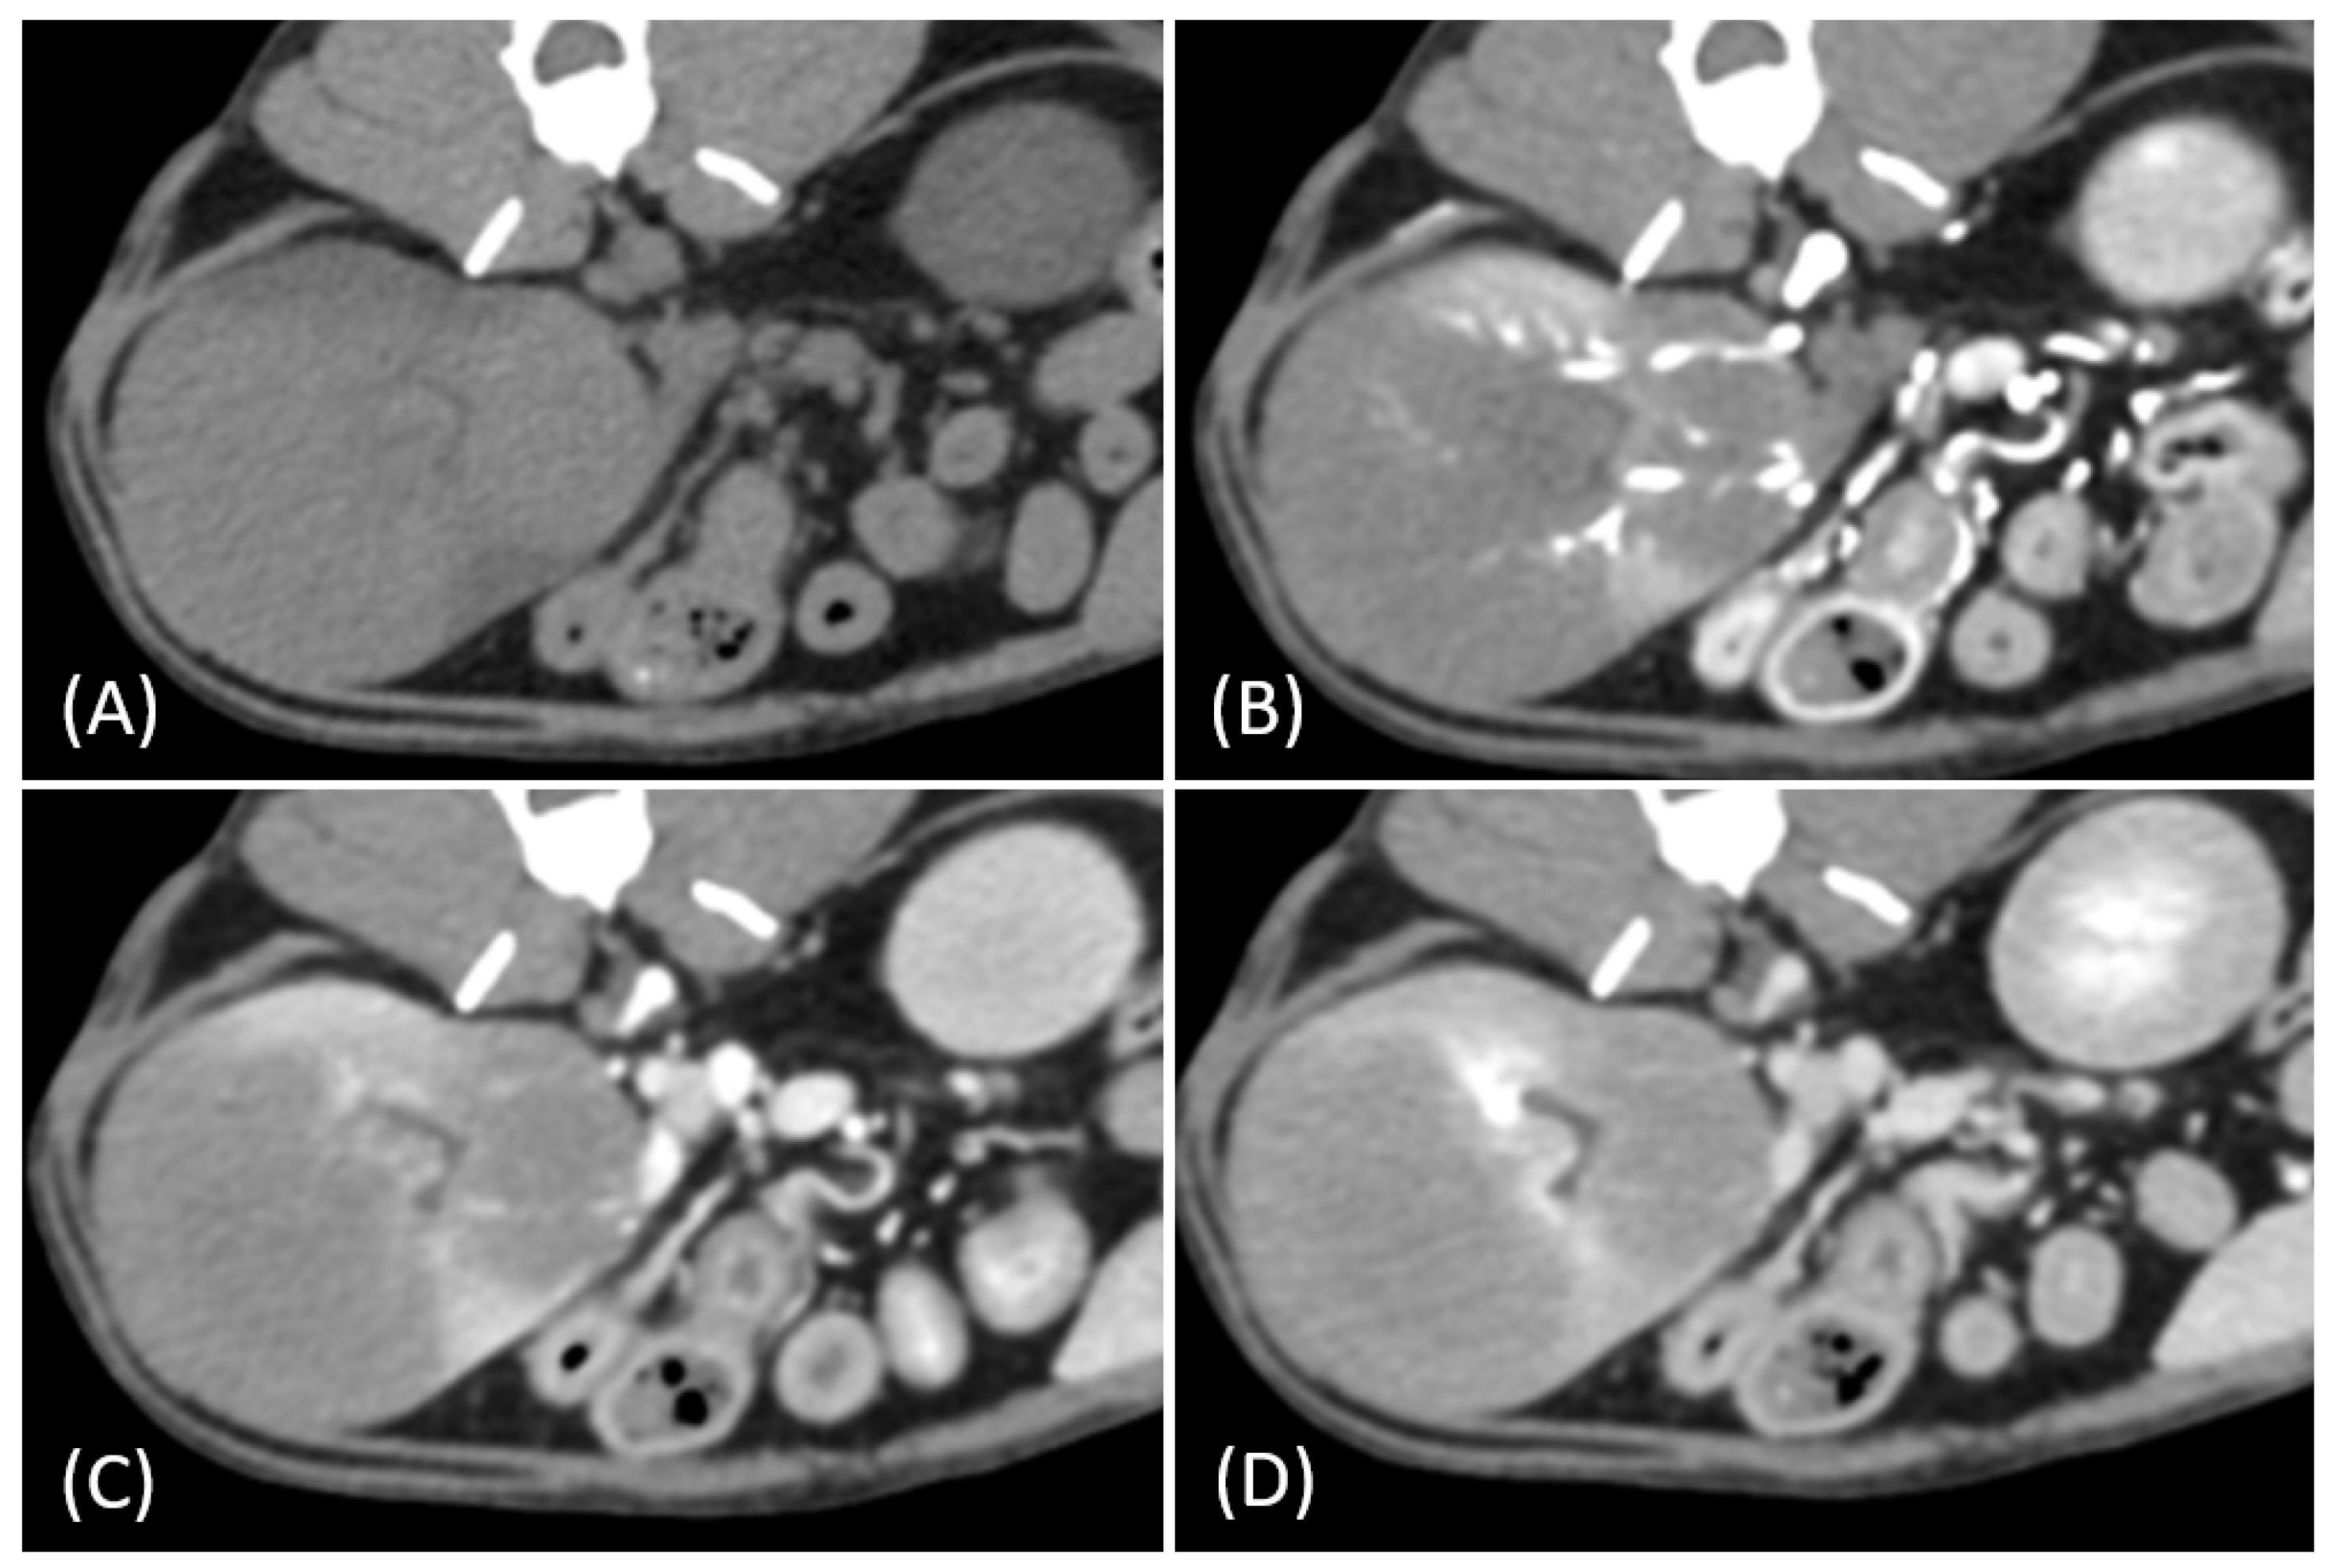

Regarding tumor distribution, RCC predominantly presented as unilateral lesions (14/15, 93.3%) (Figure 1 and Figure 2) with left kidney involvement being more common (10/15, 66.7%) than right kidney involvement (4/15, 26.7%). In contrast, lymphoma exhibited a significant tendency for bilateral involvement (6/10, 60%) (Figure 3) (p = 0.007). Additionally, one case of bilateral RCC (Figure 4) and one of unilateral primary renal lymphoma (Figure 5) were identified. The number of lesions also differed significantly between RCC and lymphoma (p < 0.001). RCC typically presented as a solitary mass (14/15, 93.3%), whereas lymphoma more commonly exhibited multiple lesions (8/10, 80%).

Figure 1.

(A) Pre-contrast, (B) corticomedullary phase, (C) nephrographic phase, and (D,E) late nephrographic/early excretory phase contrast-enhanced computed tomography (CT) images of a cat with a unilateral left renal cell carcinoma. The mass is heterogeneous, with tumor vessel enhancement (white arrow) noted in the corticomedullary phase. Progressive enhancement is observed, along with internal necrosis (black arrow). The renal vein is enlarged with tumor invasion (asterisk), but no invasion into the caudal vena cava (CVC) is seen. The tumor encases the renal artery, though definitive arterial invasion is not apparent.

Figure 2.

(A) Pre-contrast, (B) corticomedullary phase, (C) nephrographic phase, and (D,E) late nephrographic/early excretory phase contrast-enhanced computed tomography (CT) images of a cat with a unilateral left renal cell carcinoma. The tumor demonstrates predominantly heterogeneous and plateau enhancement patterns throughout the phases, with focal areas of intense enhancement visible during the corticomedullary phase.

Tumor growth patterns differed significantly between RCC and lymphoma cases (p = 0.015). RCC predominantly exhibited an expansile growth pattern (11/15, 73.3%) (Figure 1 and Figure 2), while infiltrative patterns were observed in three cases (3/15, 20%) and a combined pattern in one case (1/15, 6.7%). In contrast, lymphomas showed more variable patterns, with infiltrative growth being the most common (5/10, 50%), followed by combined (3/10, 30%) and expansile patterns (2/10, 20%) (Figure 3).

The spatial enhancement pattern differed significantly between the two tumor types (p < 0.001), with RCC typically showing heterogeneous enhancement (13/13, 100%) and lymphomas displaying homogeneous enhancement (9/10, 90%). However, one lymphoma case demonstrated a heterogeneous enhancement pattern (Figure 6A). Tumor vessel enhancement in the corticomedullary phase was observed exclusively in the RCC cases (4/5, 80%) (Figure 1B), while none of the lymphoma cases showed this feature (0/6, 0%) (p = 0.015).